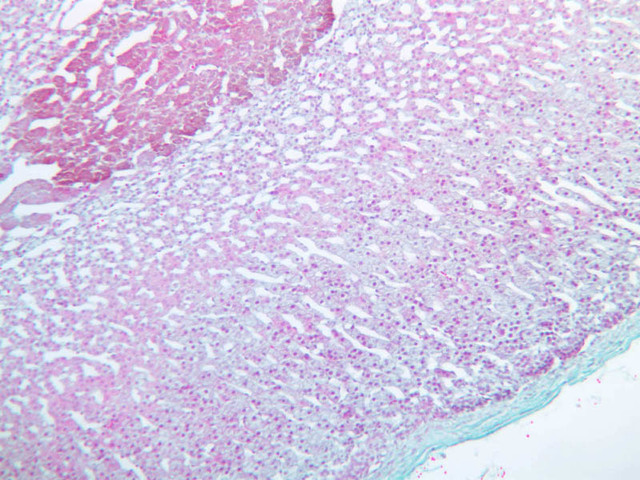

Parathyroid Glands

As a rule, four parathyroid glands, each approximately the size of an apple seed, are embedded in the connective tissue on the posterior surface of the thyroid. The polypeptide hormone produced by these glands, known as parathormone, serves to increase serum calcium and to decrease serum phosphate. Surgical removal or atrophy of these glands results in a drop of blood calcium level, muscular spasms and, ultimately, in cardiac arrest.

Examine slide B-56 (H&E [2.5x, 10x, 20x, 40x-labeled] [10x, 20x, 40x-labeled] [20x, 40x] [10x, 20x, 40x-labeled] [10x, 20x, 40x]). The connective tissue capsule of each parathyroid gland is continuous with that of the thyroid gland. It extends into the substance of the gland, dividing it into poorly defined lobules. Fat cells may separate the groups of cells and increase with age. Note the rich capillary network. The parenchyma is composed of two types of cells: (1) Principal or chief cells and (2) oxyphil cells. The polygonal chief cell is by far the more numerous cell type. Its nucleus is centrally located and has a vesicular chromatin pattern with a prominent nucleolus and its cytoplasm stains rather lightly. Oxyphil cells, which are less regular in shape and considerably larger than chief cells, are scattered singly or in small clusters. Their nuclei are smaller and more condensed than those of the chief cells and, owing to a very rich complement of mitochondria, their cytoplasm is distinctly acidophilic.